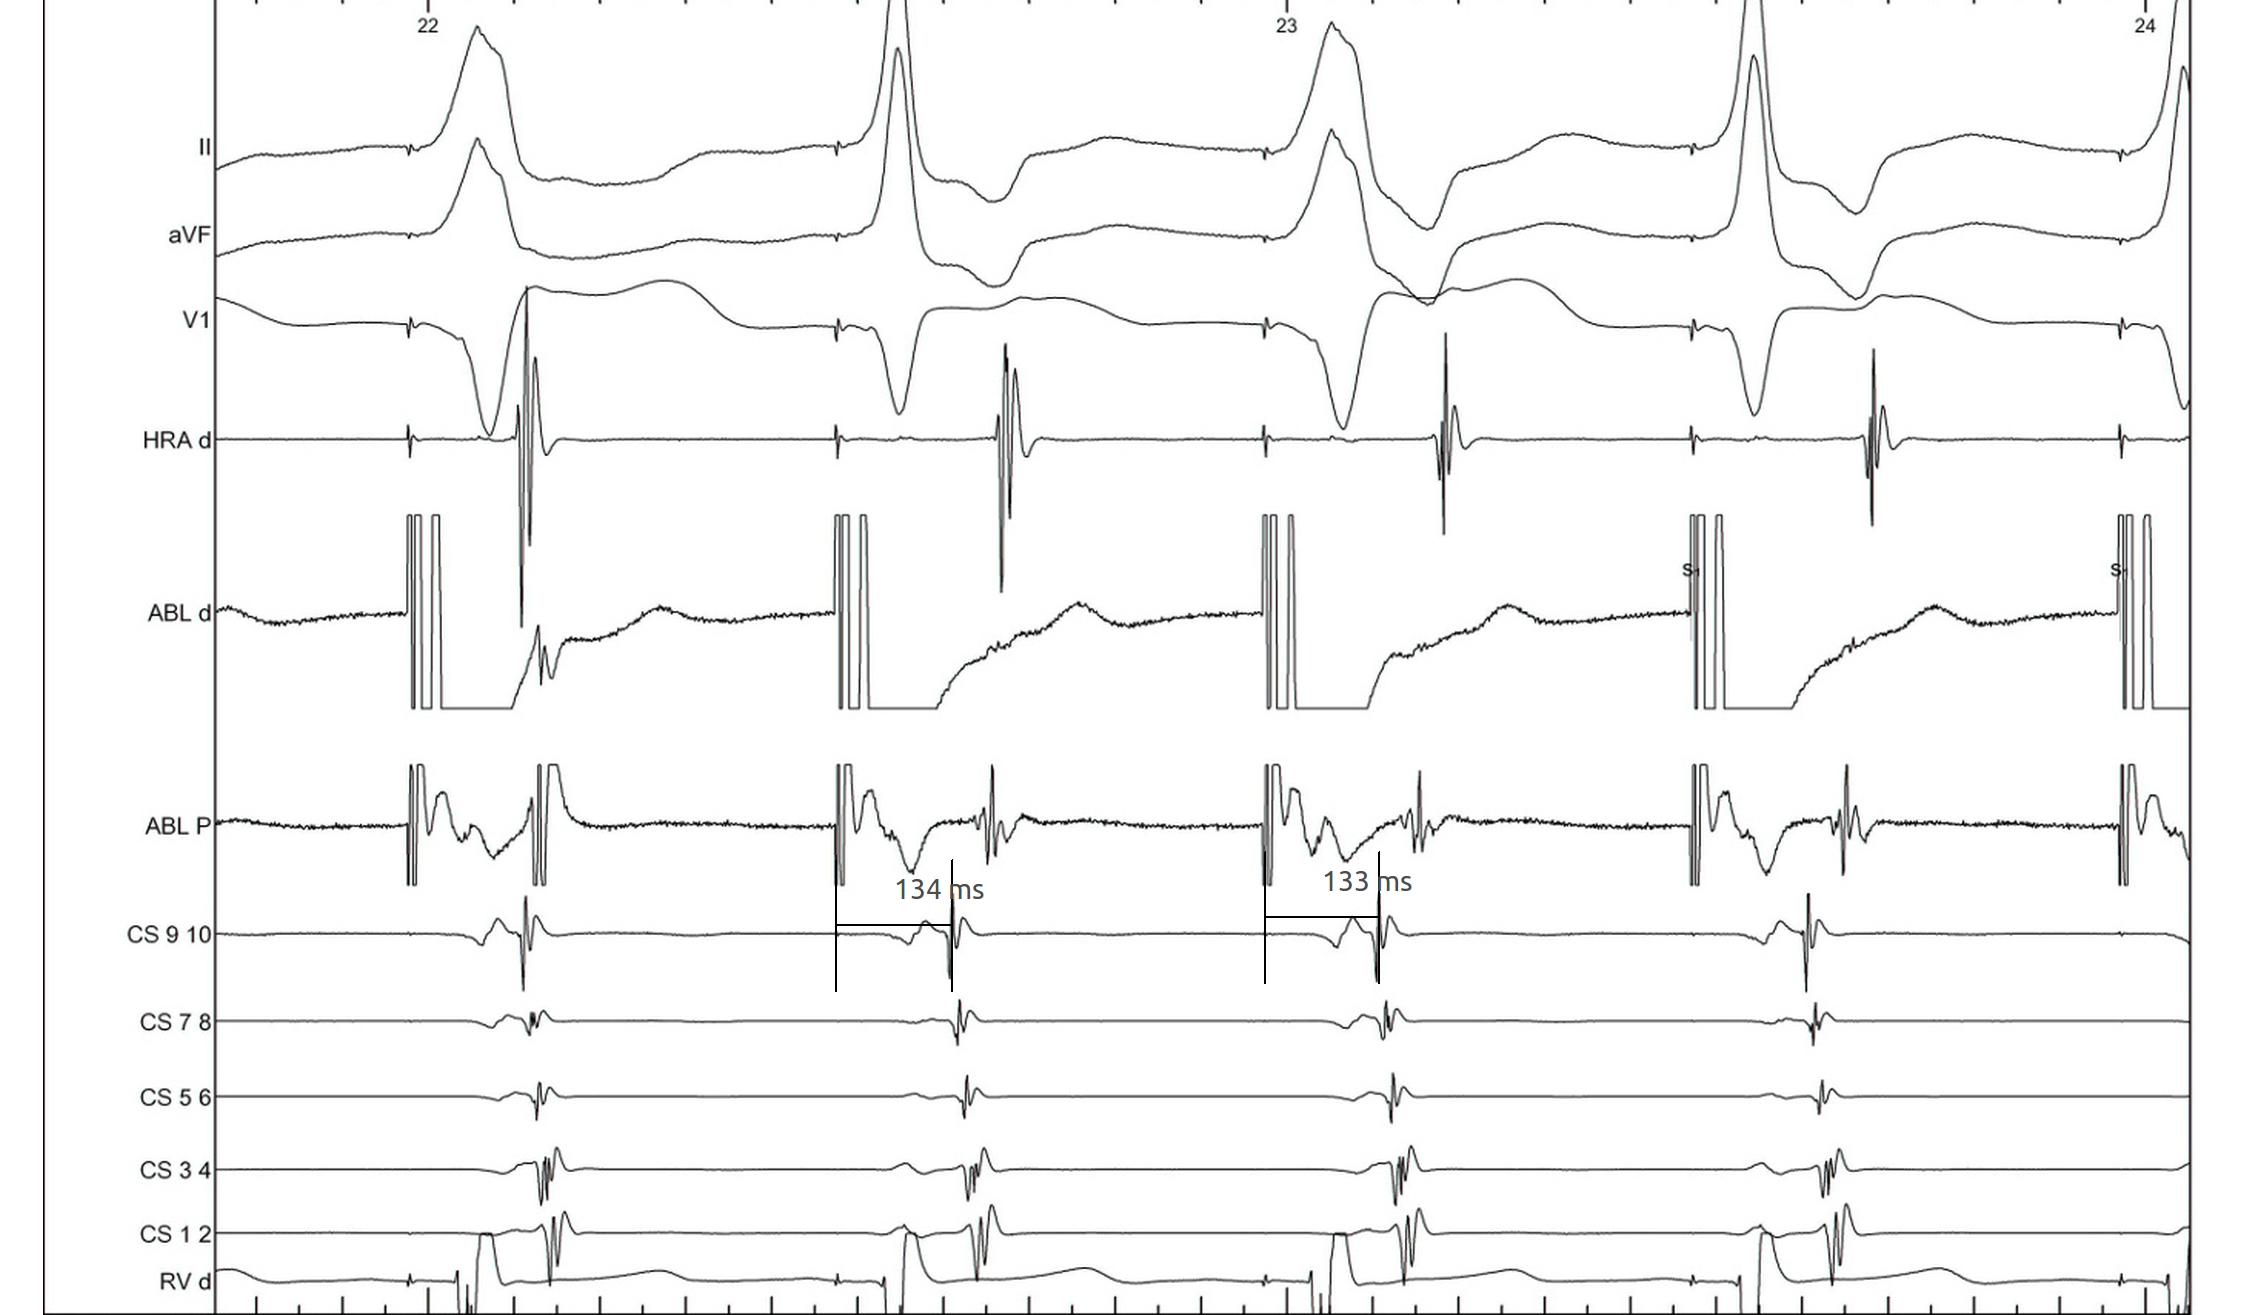

RV pacing in narrow QRS tachycardia - AVNRT / AVRT

vav_measurements_ppi.jpg

SA / VA intervals

sa_va.jpg